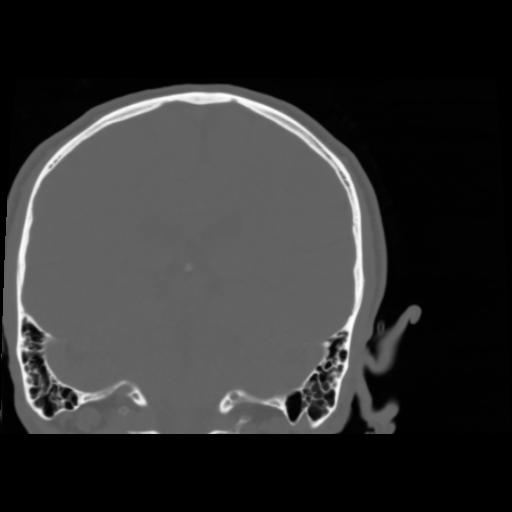

5 CEREBRO,,Coronal,3.000,CEREBRO,Coronal,